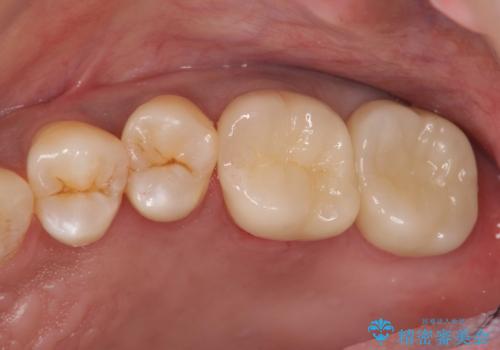

- 24.2万円(ジルコニアクラウン・仮歯・部分矯正)費用は治療当時の料金となります

90°ねじれてしまっていた歯を、矯正治療で治し、前後の歯の咬合関係も改善してしっかりと噛めるようになりました。